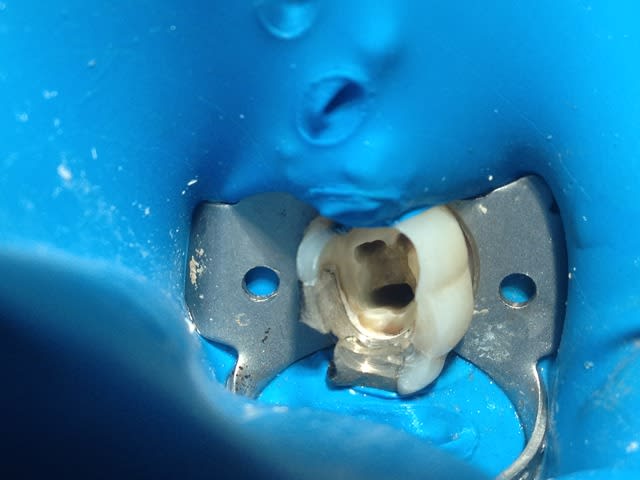

Je suis pas endo exclusif, une des différences (hormis le tarif environ de 5 à 10 fois moins cher, faut pas déconner) se situe dans la cavité d'accès prête à recevoir le spr 57.

Photo prise avec iphone 4s déductible !)))))